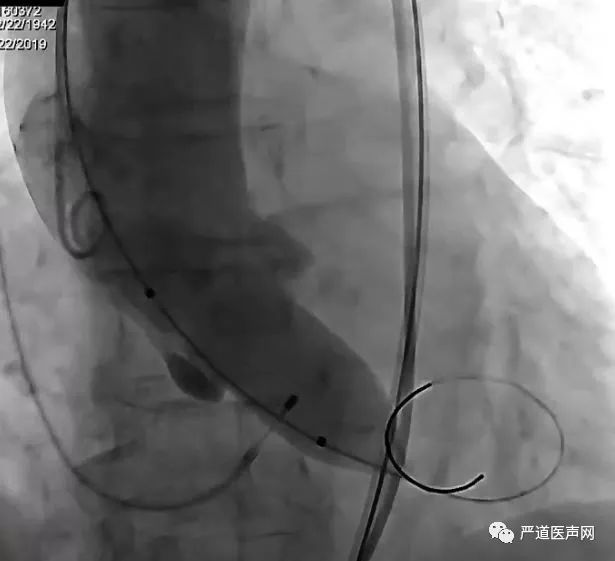

TAVR瓣膜释放过程

通过22F血管鞘置入VenusA-Plus瓣膜,并顺利过主动脉弓,跨越瓣膜,造影确定瓣膜位置, 确定瓣膜Mark点与瓣环平行,逐步释放部分瓣膜,瓣膜裙边展开,保持瓣膜位置,造影提示瓣膜位置良好,开始慢速释放瓣膜,待裙边完全展开,开始130次/分快心室率起搏,确保瓣膜释放过程位置稳定,继续释放瓣膜,再次造影提示位置良好,快速释放瓣膜。

回收置入器,瓣膜释放后因存在瓣周漏,故采用23mm球囊进行后扩张一次,术后TEE提示,支架瓣膜展开基本完全,TEE及造影提示轻度PVL。

瓣膜血流动力学效果满意。测量左心室压力136/2mmHg,升主动脉压力134/55mmHg,跨瓣压力<5mmHg,手术效果满意。

TAVR-VenusA-Plus植入后

手术演示中